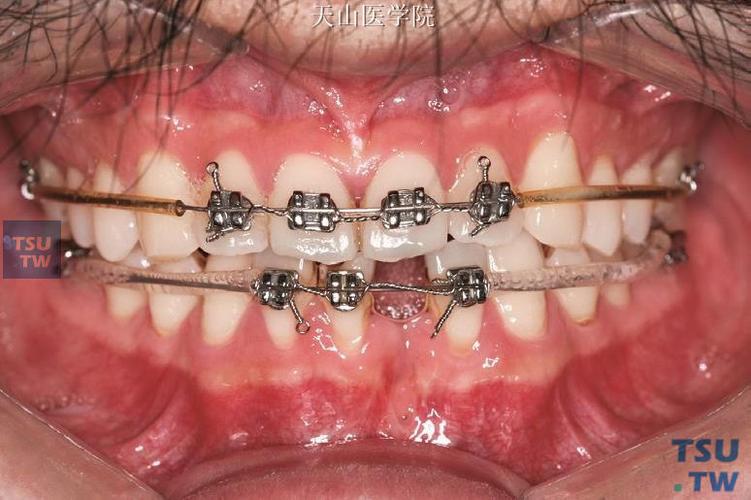

用细丝钳尖端夹持弯制点,向远中方向弯曲弓丝,形成“U”形或“Ω”形曲,曲的高度(曲顶到弓丝基底的距离)控制在3-5mm,高度不足则力量弱,过高易导致弓丝变形或患者不适,曲的宽度(曲的近远中径)约2-3mm,确保能容纳于磨牙后间隙。

(图片来源网络,侵删) -